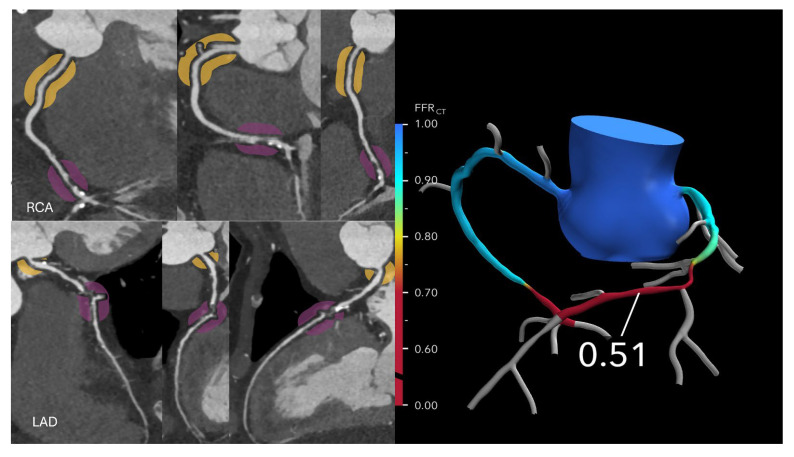

Coronary computed tomography angiography (CCTA) has emerged as the leading noninvasive imaging modality for the assessment of coronary artery disease (CAD), offering high-resolution visualization of the coronary anatomy and plaque characterization. The development of fractional flow reserve derived from CCTA (FFR-CT) has further transformed the diagnostic landscape by enabling the simultaneous evaluation of both anatomical stenosis and lesion-specific ischemia. FFR-CT has demonstrated diagnostic accuracy comparable to invasive FFR. The combined use of CCTA and FFR-CT is now pivotal in a broad range of clinical scenarios, including the evaluation of stable and acute chest pain, assessment of high-risk and complex plaque features, and preoperative planning. As evidence continues to mount, CCTA and FFR-CT are positioned to become the primary gatekeepers to the cardiac catheterization laboratory, potentially reducing the number of unnecessary invasive procedures. This review highlights the growing clinical utility of FFR-CT, its integration with advanced plaque imaging, and the future potential of these technologies in redefining the management of CAD, while also acknowledging current limitations, including image quality requirements, cost, and access.